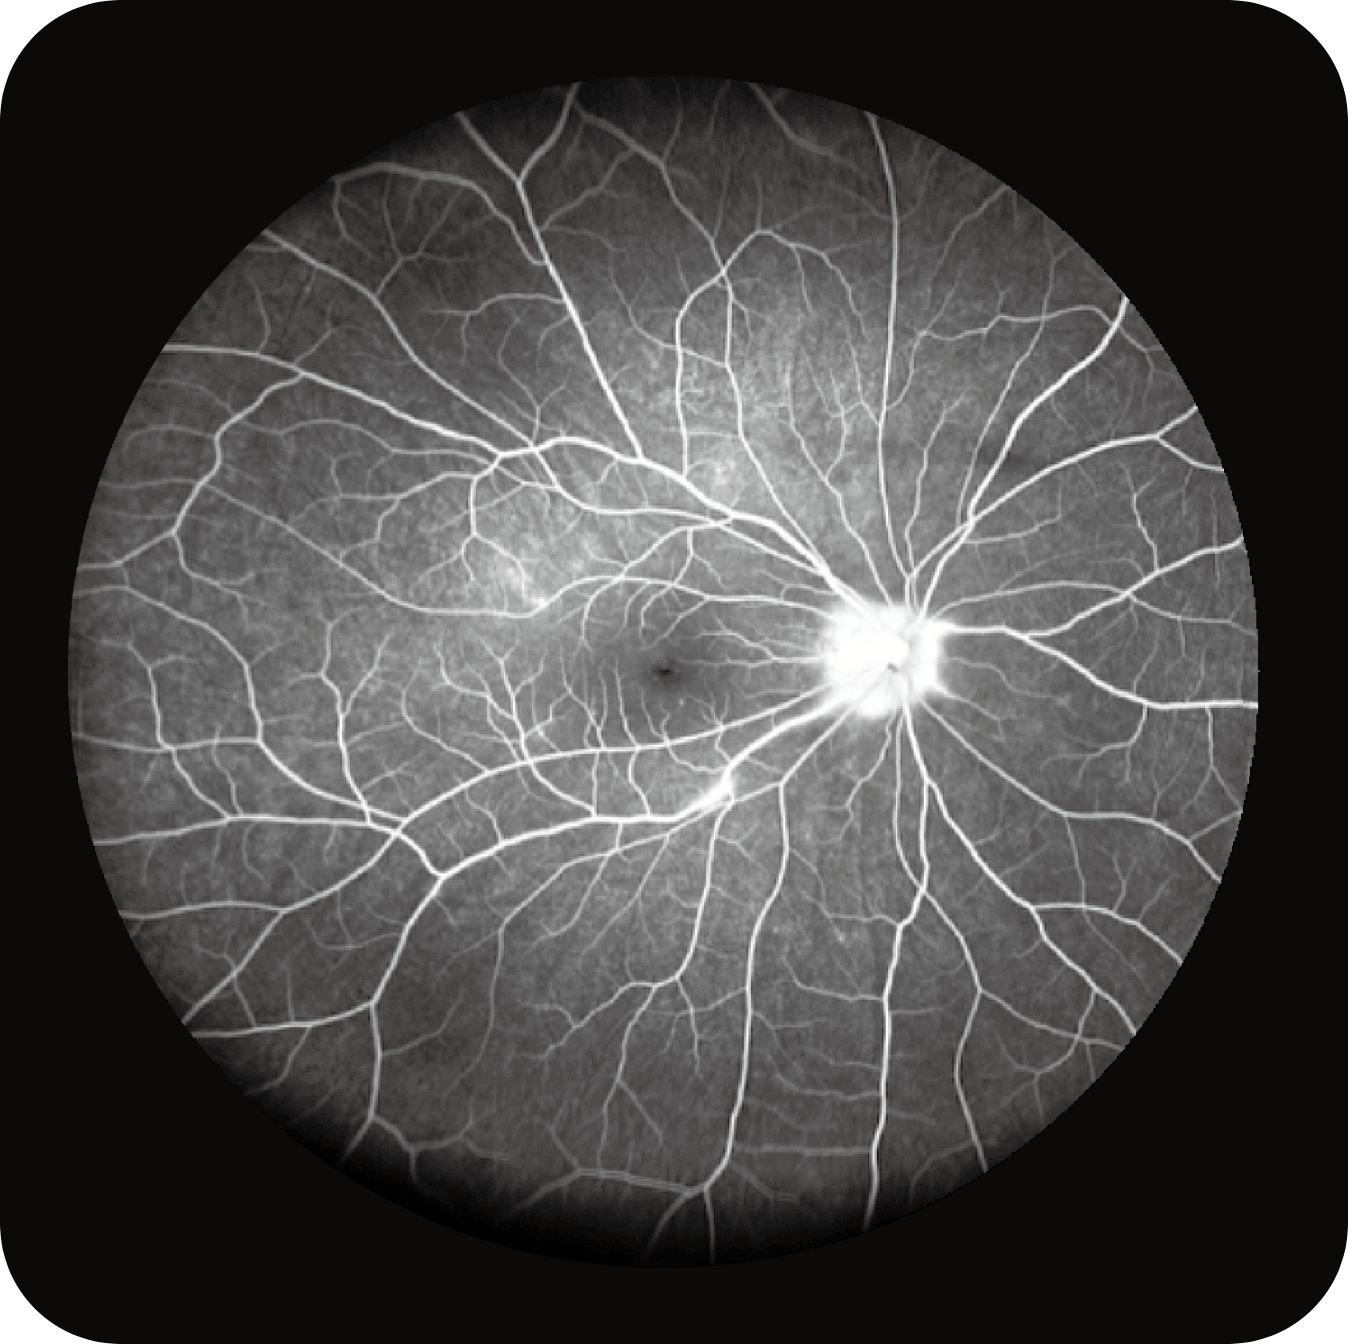

Multi-Modalidade

Altamente integrado com tecnologias como SLO confocal e SS-OCT, ele combina imagens coloridas SLO de campo ultralargo, angiografia confocal a laser, autofluorescência e imagens tomográficas de segmento anterior e posterior ultraamplas e profundas em um único sistema.

Angiografia multimodal (FA e ICG – disponível nas versões avançadas).

OCTA até 220° em mosaico, para análise detalhada da vascularização.